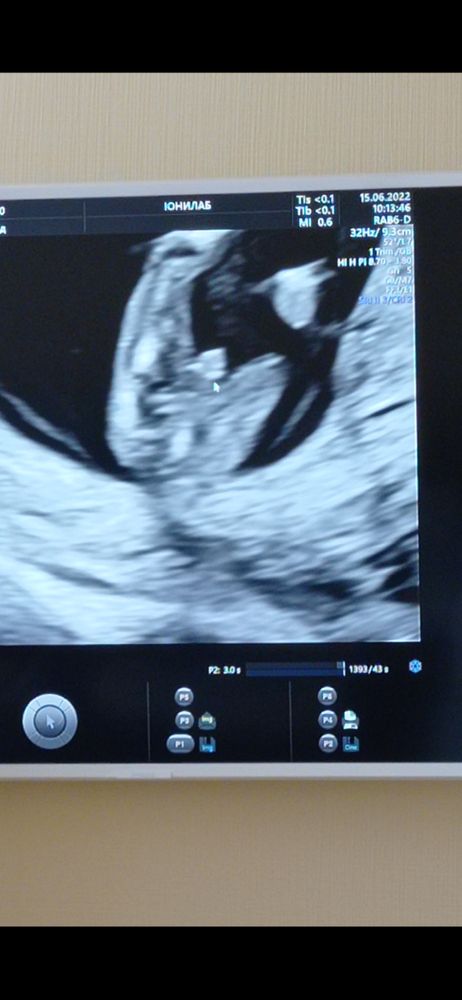

Вид моего малыша в 12 недель снизу. Это же не может быть девочка? Очевидные яйца. (Пс первые две дочки)

Посмешили. Никакие это не яички. В 12 недель яички ещё находятся внутри брюшной полости. При подобной проекции определить пол плода невозможно на вашем сроке, это половой бугорок и складки ткани, из которых потом формируется мошонка или половые губы. Пол сейчас можно определить только по углу наклона полового бугорка ( для этого нужен вид сбоку)

Это не яйца, это половой бугорок, в этом ракурсе он такой же и у девочек на этом сроке.

У меня на 12+5 смотрели с попы малыша и предположили верно, УЗИ врач хорошая, второй скрининг специально пошла делать у нее. На этом сроке с попы там штучка у мальчика точно видно хорошо (если оборудование позволяет), но на данном снимке я не вижу четко этой штучки, мне кажется это пуповина (крупный объект между ног). К сожалению фото моего скрининга нет, в интернете видела дважды, чтобы было как у моего малыша на этом сроке, найду - прикреплю ниже. Мне кажется пуповина.

Мошонка такая в 16-17 недель, а вот в 12-13 не помню такого объема в этой области. Но все возможно. Будем надеяться мальчик!

Tarantina, а это уже мой малыш на 17 неделе - тут уже прямо яйки висят) Во время второго скрининга фоток не было в 20+5 недели, но на втором скрининге там уже все выглядело как обычно у младенцев уже, даже гадать не нужно. Просто ваш снимок напоминает мне то, что у нас вот на 17й. На 12 неделе ничего ещё не висело, а такая штулька торчала. Вот поэтому и думаю, вдруг пуповина... хотя я когда свой снимок впервые глянула - тоже подумала вдруг пуповина)

Anastasi-z, всё поняла теперь про какую штучку вы говорите, про эту пипеточку как будто. Да у моего такой нету. Может там девка блин